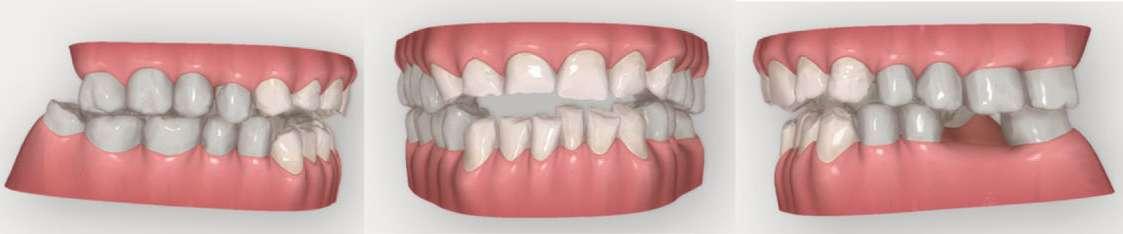

Figura 1-3. Secuencia fotográfica extraoral inicial.

Figura 4-6. Análisis de la sonrisa del paciente.